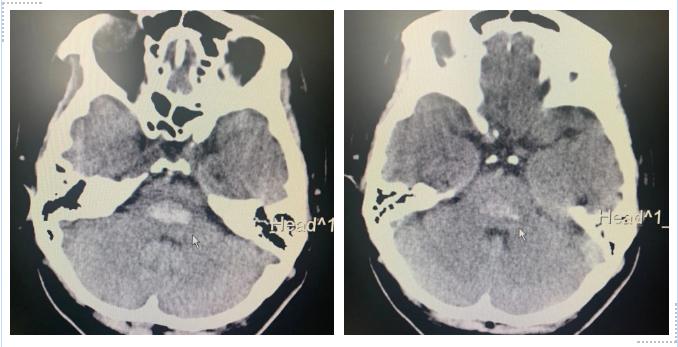

果然,頭顱CT檢查明確了這一診斷:腦干(腦橋區(qū))出血。

3、腦干出血的診斷

顱腦CT掃描為腦干診斷的首選??芍苯佑^察到血腫的部位和量,而且對預(yù)后也能做出較正確的評估。